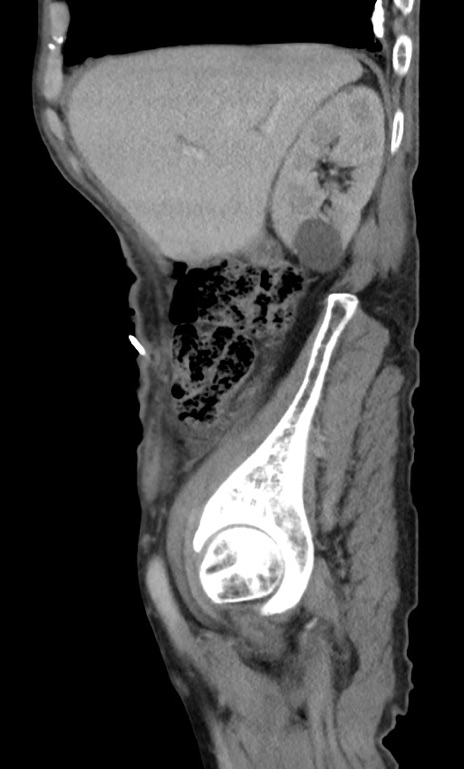

症例3(矢状断像)

【症例】 70歳代男性

【主訴】右鼠径部腫瘤、疼痛

【現病歴】本日朝より上記主訴あり、受診。

【既往歴】膀胱癌にて膀胱全摘、両側尿管皮膚瘻

【データ】WBC 5600、CRP 0.56